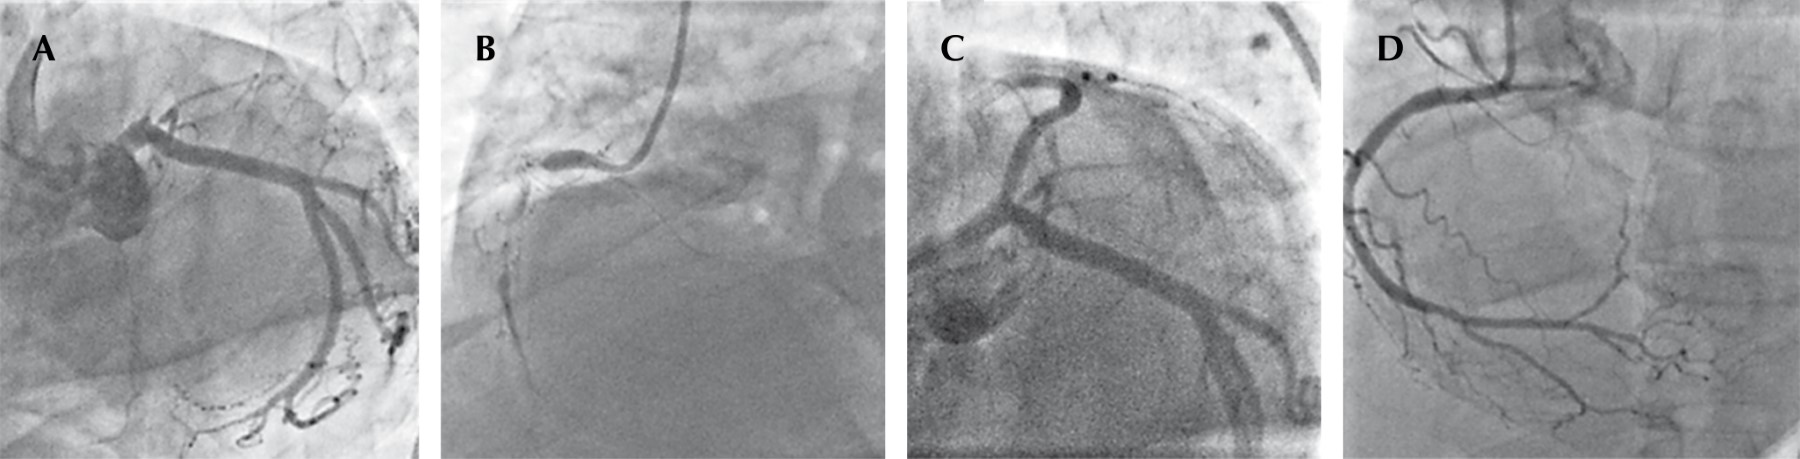

Trombosis coronaria multivaso y ruptura septal interventricular postinfarto de miocardio con elevación del ST, presentación inusual

La trombosis multivaso es un hallazgo poco común en la angiografía coronaria. La ruptura septal ventricular es una complicación mecánica con alta mortalidad en el infarto agudo de miocardio, siendo necesario un tratamiento invasivo de emergencia. La asociación de estas entidades no ha sido reportada en la literatura médica. Este artículo presenta el caso clínico de un paciente con infarto agudo de miocardio sometido a trombólisis, coronariografía, intervención coronaria percutánea y cirugía de urgencia por trombosis coronaria simultánea de descendente anterior y coronaria derecha con rotura interventricular, choque cardiogénico refractario y muerte.

Figura 1

Figura 2

Figura 3

Figura 4

Figura 5

Figura 6